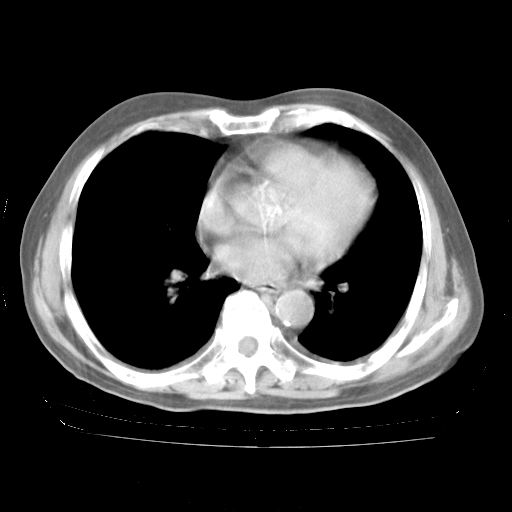

4月28日肺部CT——再次出现类似去年5月9日——透光度降低,“间质性”改变。

4月28日肺部CT